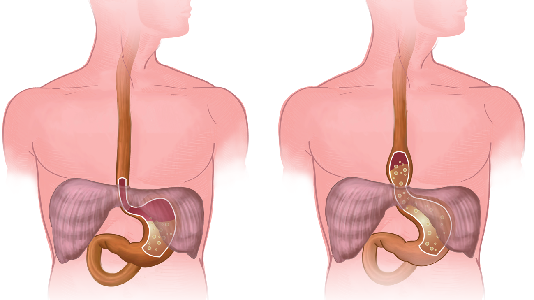

Detailreiche Fotografien aus der medizinischen Praxis ergänzen die Texte; moderne, genaue,

wissenschaftliche Zeichnungen geben Einblick in die Anatomie und die Funktion der Lunge und

anderer Organe.